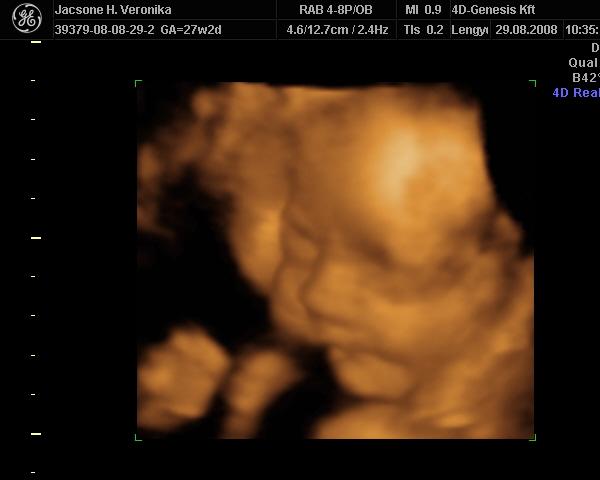

30. hét: Kép Kép

Bernuska: nekem csak a doki magánrendelésén van UH. Én nem járok máshová. Kérdeztem erről a védőnőt is, de ő azt mondta a doki elég. Mondjuk ott nagyon jó minőségű UH van, a környék legjobb 4D-se (amúgy is csak a kórházban van, az meg pocsék). Szívhangot nem néz, de a védőnő mindig nézi. Most azért is mért a doki, mert ez protokoll UH volt, így a 30 .hét környékén, a súlyt csak saccolta, de azt mondta, hogy ott nagyot lehet bukni. 3 hete például megnézte a méhszájamat, és akkor is UH-zott csak nem mért. Akkor végignézte a feje búbjától a kis talpáig az egész gyerkőcöt, és ott külön megnézte a szívét. Ja és mindjárt az elején mikor megnézte a fejecskéjét áttette 4D-re és akkor kaptunk róla egy szép képet. Most is megvizsgált, tökéletesen zárt minden, aztán UH-zott. Megint a fejével kezdte, átrakta 4D-re, úgy nézegettük egy kicsit és jókat nevettünk a dokival. Teljesen eltakarta magát a gyerek és fintorgott. A doki is megjegyezte, hogy milyen kis helyes. Aztán nagy nehezen az egyik kezét elhúzta, és azt a képet kinyomtatta a doki (nemsokára felteszem), Ezután visszakapcsolta sima UH-ra és megmérte! Utána meg kérdezhettem, amit akarok. Nagyon-nagyon segítőkész a dokim, bármikor hívhatom. Pedig én nagyon féltem, mert nincs még egy éve hogy hozzá járok. Előtte 10 évig egy másik dokihoz jártam, akit nagyon szerettem, de elment nyugdíjba és szülést nem vállal. Akkor találtam rá a mostanira. Eddig minden ok vele. Ja és szerintem nem is drága, mert 5000Ft egy vizsgálat. Itt a környéken más dokik is elkérnek ennyit, aztán még UH-juk sincsen. Ja van internetes oldaluk is www.medi-centrumszekszard.hu. Itt azért látható, hogy mennyire kultúrált is. Ha látnád az itteni kórházat, háááátttt pocsék!!! :twisted: Elég lesz ott szülni!!!

Íme a trónörökösünk!

Kép 29. hét